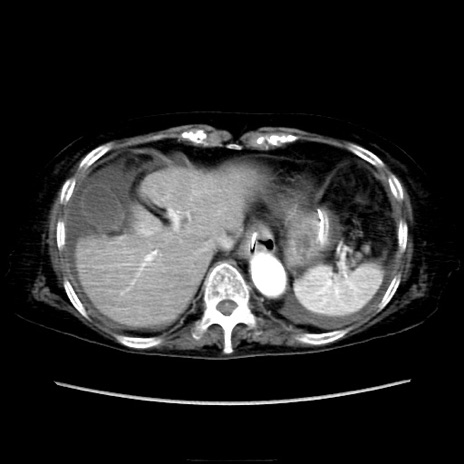

症例40(横断像)

【症例】90歳代女性

【主訴】腹痛・嘔吐

【現病歴】 食欲低下、嘔吐があり昨日他院受診。肺炎と診断され入院となる。入院後より腹部全体に圧痛あり。胃管留置され経過みていたが、症状持続するため、

当院転院となる。

【既往歴】胸椎圧迫骨折、胆石症

【身体所見】腹部:中央に激痛あり、圧痛あり、反跳痛不明

【データ】WBC 17100、CRP 18.82